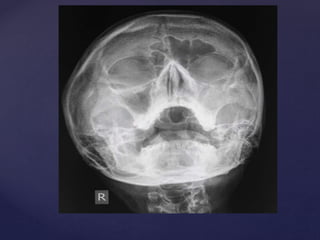

 Plain X Ray Skull

 Lateral View

 Showing soft tissue

shadow in the roof and

posterior wall of

nasopharynx.

 For Adenoid

hypertrophy

 Occluding the airway

 Ch. Adenoiditis